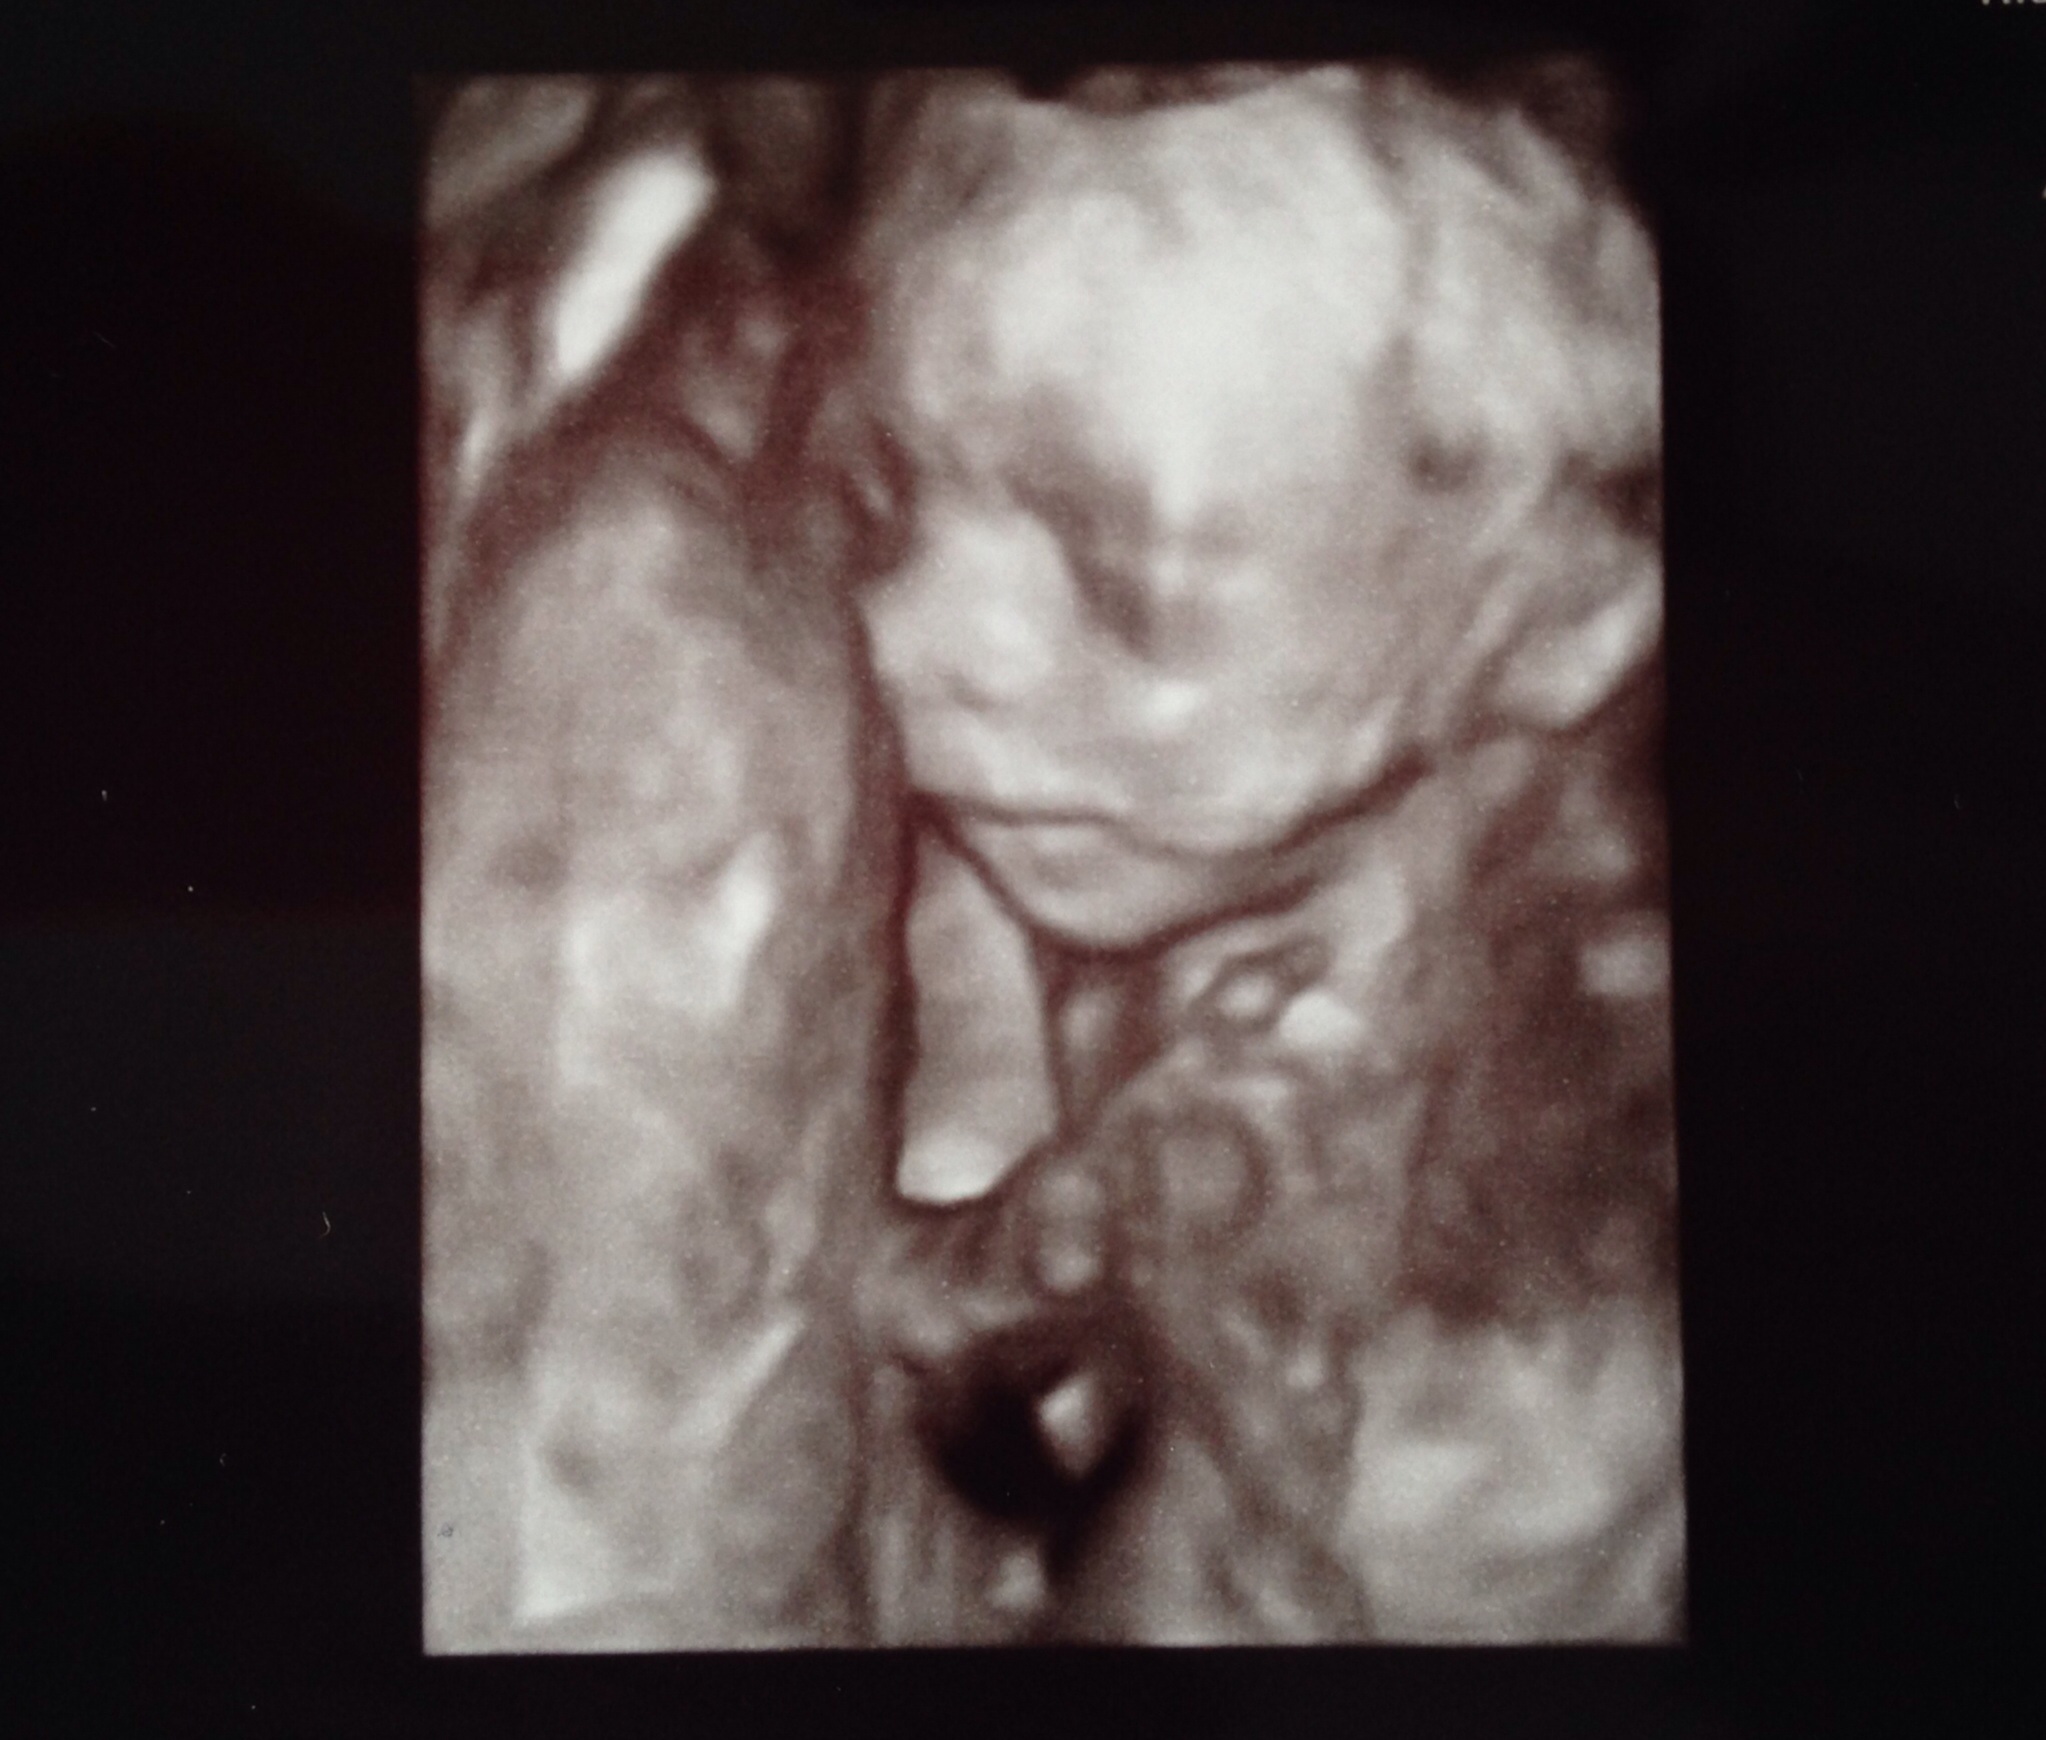

• So, I just got home from my A/S and baby is big and healthy! (baby has a big head too haha) Baby is very active and was kicking up a storm on the monitor. lol It looked like the baby was waving too. hehehe I cried before the A/S, during and I'm crying now after seeing my little nugget. I just can't believe this is happening.

And....

image

lol it's another boy!!! 3 boys and 1 girl. DW and I are thrilled :)